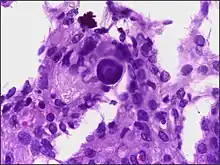

Although the majority of meningiomas are benign, they may have malignant presentations. Classification of meningiomas are based upon the WHO classification system.[23]

- Benign (Grade I) – (90%) – meningothelial, fibrous, transitional, psammomatous, angioblastic

- Atypical (Grade II) – (7%) – chordoid, clear cell, atypical (includes brain invasion)

- Anaplastic/malignant (Grade III) – (2%) – papillary, rhabdoid, anaplastic (most aggressive)

In a 2008 review of the latter two categories, atypical and anaplastic-meningioma cases, the mean overall survival for atypical meningiomas was found to be 11.9 years vs. 3.3 years for anaplastic meningiomas. Mean relapse-free survival for atypical meningiomas was 11.5 years vs. 2.7 years for anaplastic meningiomas.[24]

Malignant anaplastic meningioma is aggressive. Although anaplastic meningioma has higher chances of distant metastasis than the other two types, the overall incidence of meningioma metastasis is only 0.18%; which is considered rare.[25] Even if, by general rule, neoplasms of the nervous system (brain tumors) cannot metastasize into the body because of the blood–brain barrier, anaplastic meningioma can. Although they are inside the cerebral cavity, they are located on the bloodside of the BBB, because meningiomas tend to be connected to blood vessels. Thus, cancerized cells can escape into the bloodstream, which is why meningiomas, when they metastasize, often turn up around the lungs.

Anaplastic meningioma and hemangiopericytoma are difficult to distinguish, even by pathological means, as they look similar, especially, if the first occurrence is a meningeal tumor, and both tumors occur in the same types of tissue.